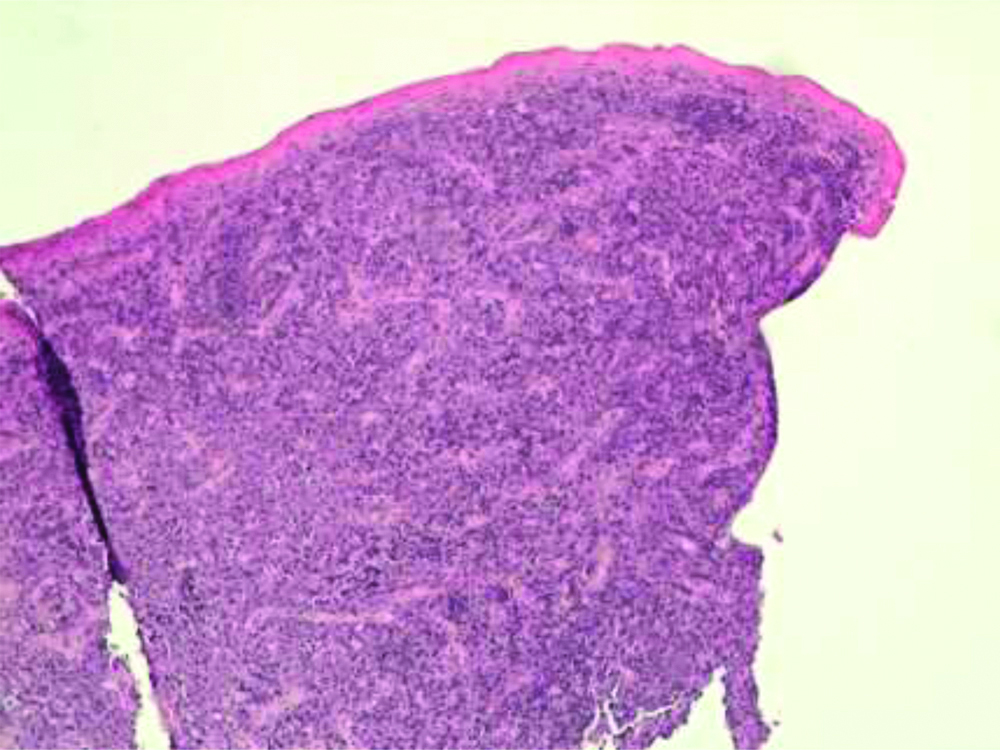

There were no monoclonal bands to urinary immunofixation, and a negative Bence Jones proteinuria. In serum immunofixation, there was a mild monoclonal component in the gamma area typified as IgG Lambda light chains in a framework of hypergammaglobulinemia. The patient had chronic esotoxic hepatopathy but with explorable superficial lymph node stations. An incisional biopsy involving the base of the lesion and the surrounding healthy gingiva was performed. The histological examination, under a Leica DMD108 microscope (Leica Camera AG, Wetzlar, Germany) found infiltration of the oral mucosa by a monomorphic population of large lymphoid elements with morphological characteristics similar to immunoblasts [Table/Fig-3].

The submucosa was infiltrated by numerous blast cells with brisk mitotic activity, and diffuse growth pattern (H&E, magnification x10).